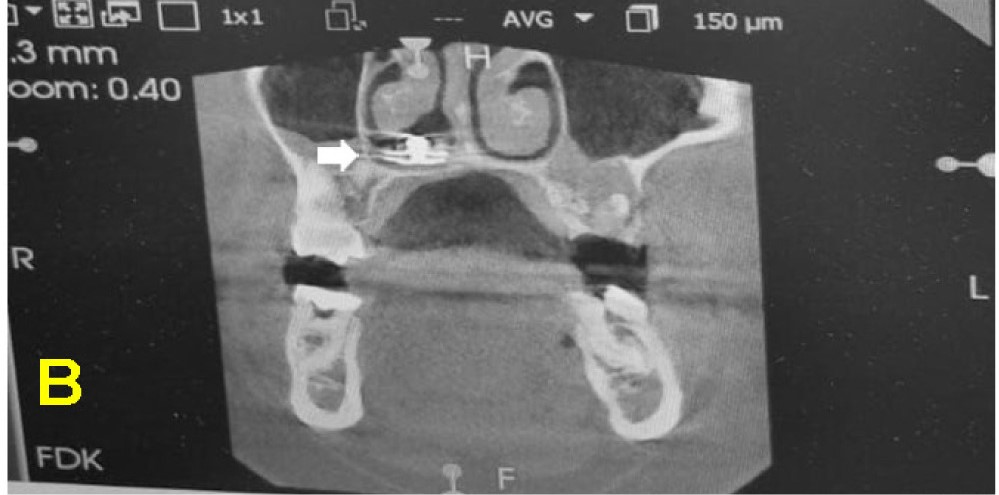

“A CBCT confirmed the presence of the foreign body with associated mild inflammation, but no significant bony damage or sinus involvement was observed.

“With informed consent from the patient’s parent, the foreign body was removed under local anaesthesia in a semi-sitting position to reduce the risk of dislodgment to the airway.”